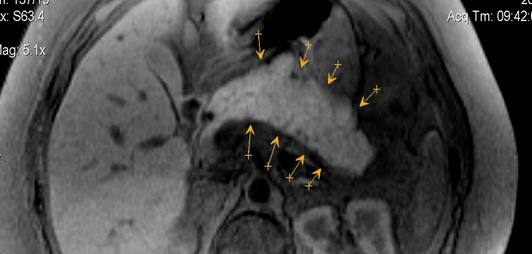

Панкреонекроз диагностика

Панкреонекроз диагностика 115 фото